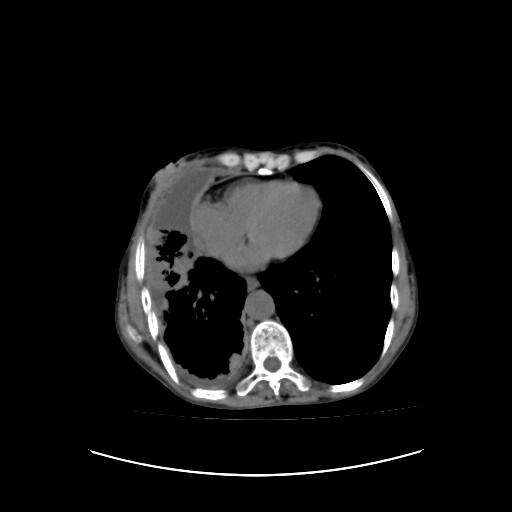

可见多发肺内病灶,且胸膜病灶较多有圆球状而非丘状,多考虑胸膜转移瘤伴胸腔积液,右侧胸廓缩小固定,且部分病灶呈丘状,尚不除外恶性胸膜间皮瘤伴肺内转移

右侧胸膜增厚,局部呈结节状增厚,右侧胸腔少量积液。双肺未见确切肿块影。纵隔未见淋巴结肿大。气管、支气管通畅。考虑右侧胸膜间皮瘤(恶性?)可能性大。不除外癌性胸膜炎。

恶性胸膜间皮瘤伴肺内转移可能性大;或胸膜、肺内均为转移瘤,左肺下叶亦见多发小结节影。

右侧胸廓塌陷,右侧胸膜广泛增厚并见多发胸膜结节,右侧少量胸腔积液并包裹。

右侧广泛胸膜增厚,局部呈结节状增厚,右侧胸腔少量积液。双肺未见确切肿块影。纵隔未见淋巴结肿大。气管、支气管通畅。考虑右侧胸膜间皮瘤(恶性?)可能性大。支持!

右侧胸膜转移瘤,原发灶可能就在在右肺,另外建议检查右侧乳腺.

右胸腔结节均考虑来自胸膜(部分来源于叶裂),考虑胸膜间皮瘤或转移瘤.